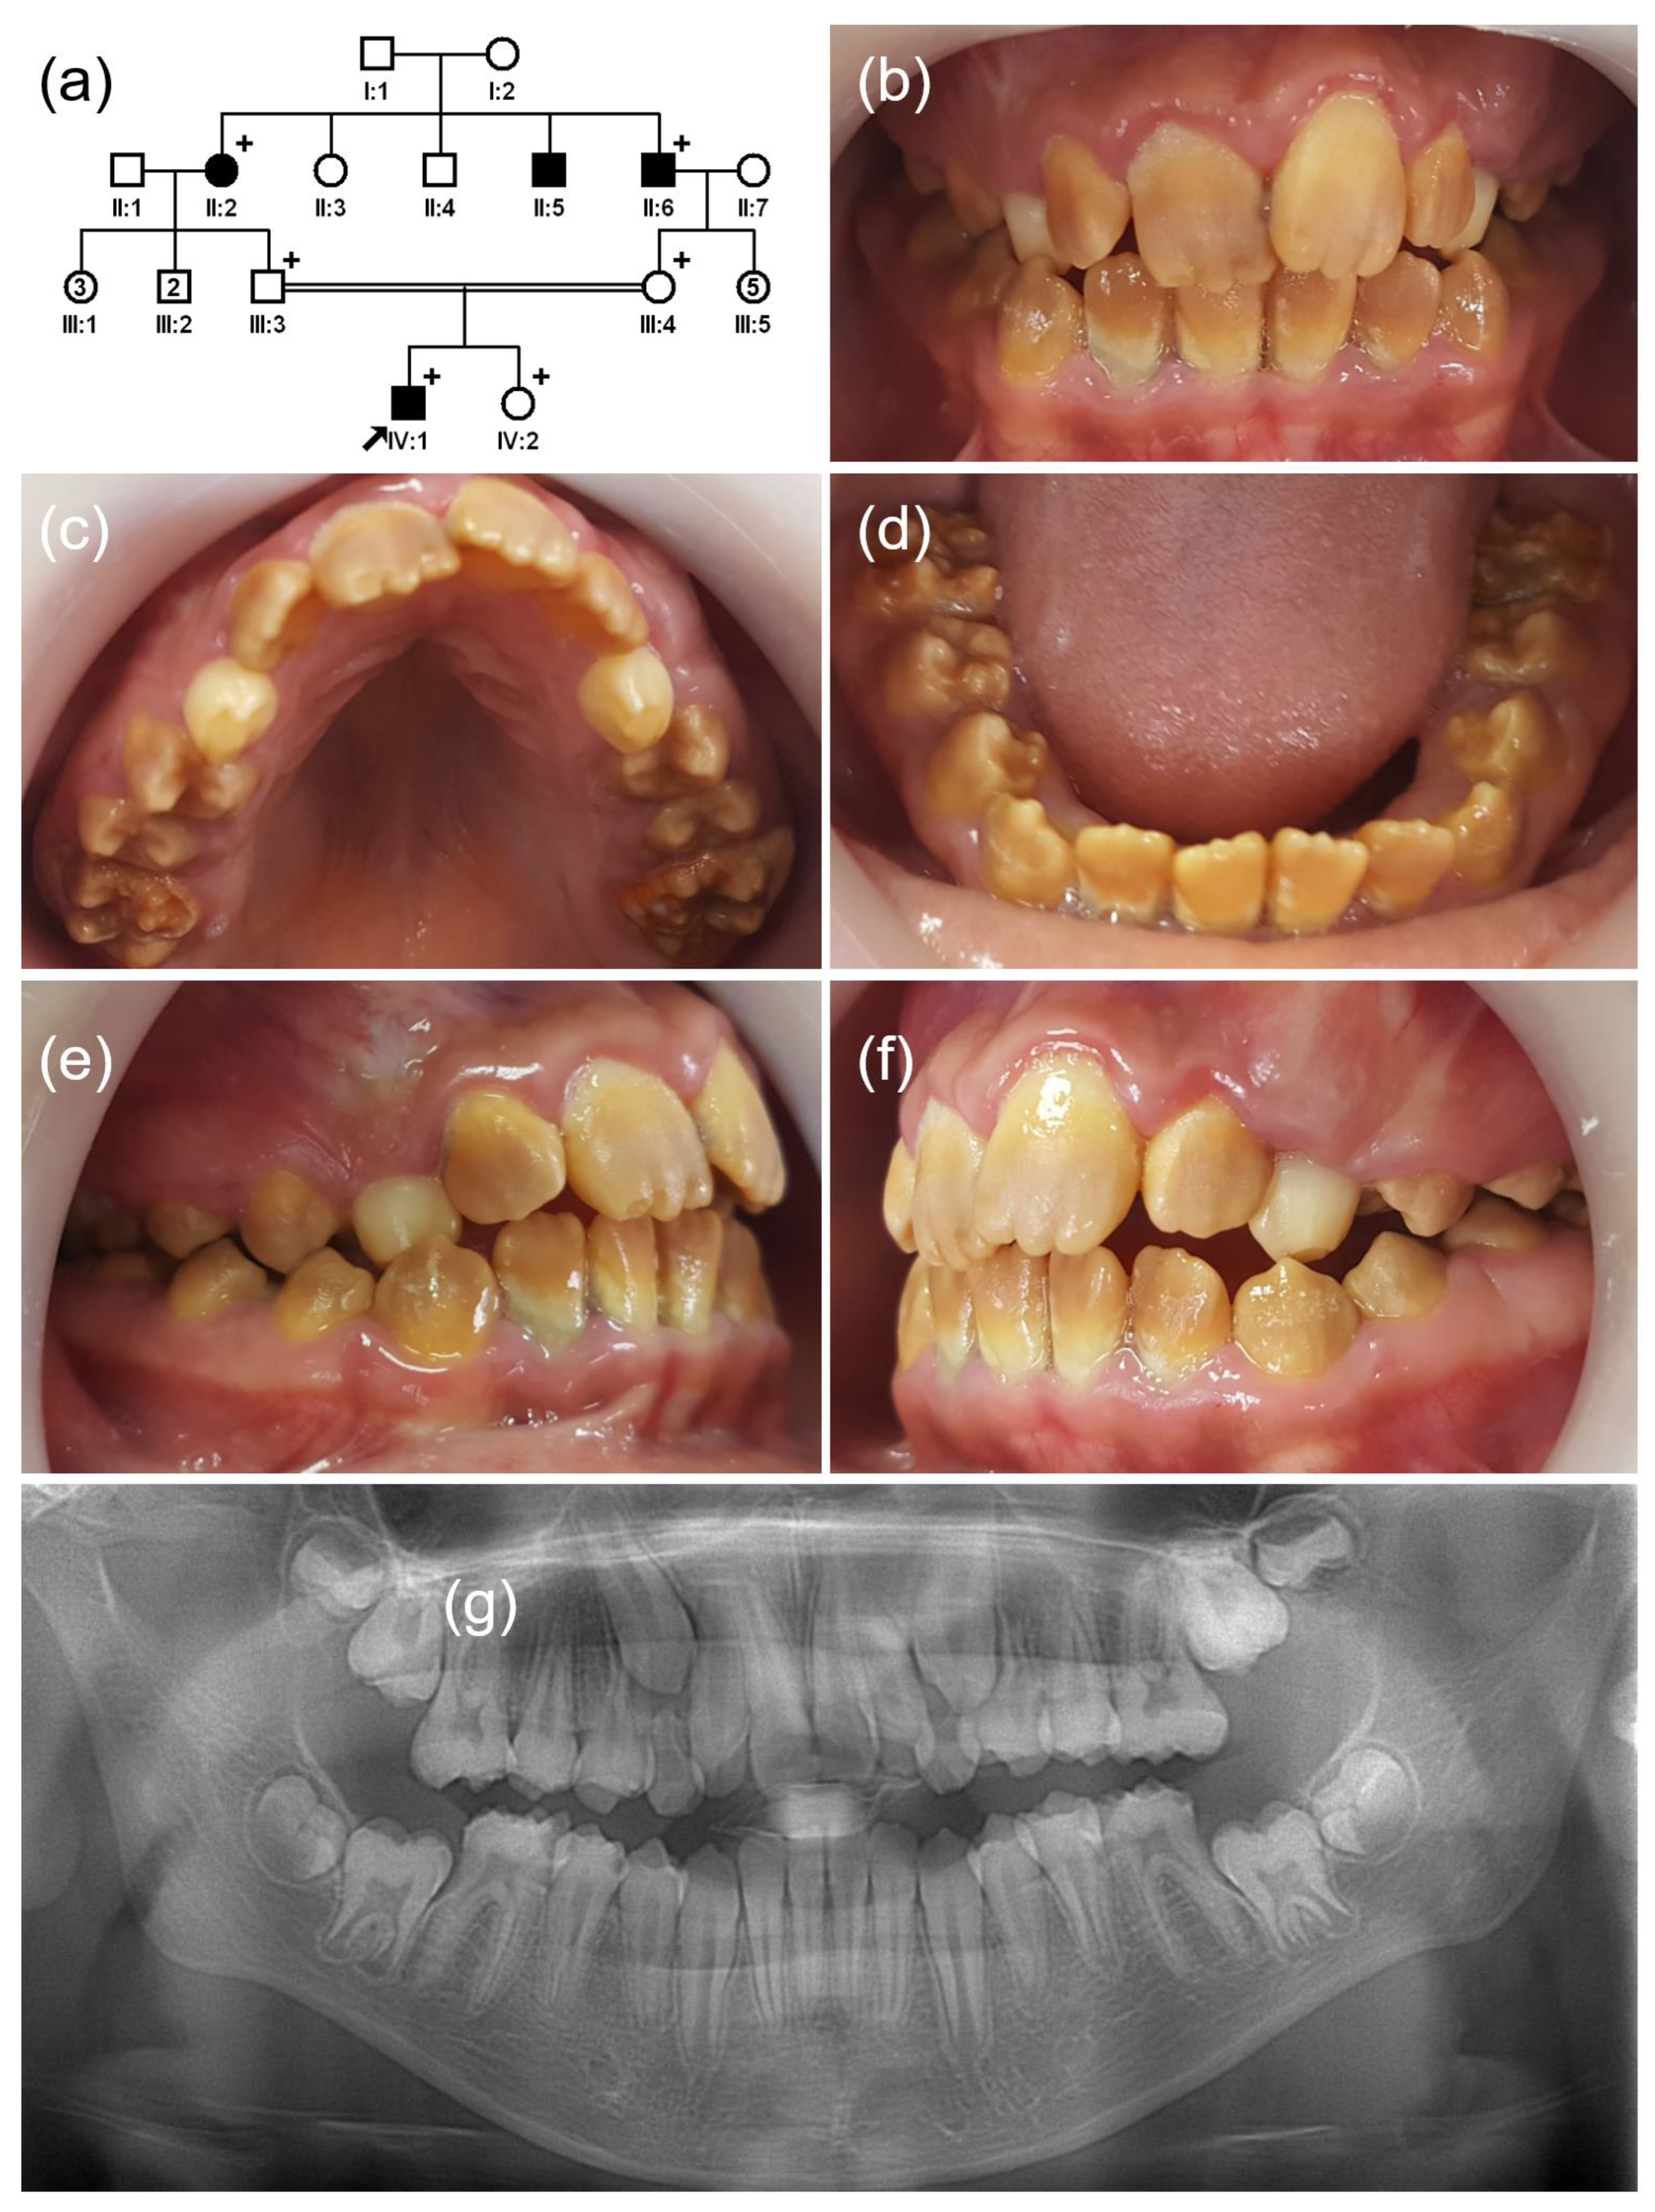

3.3. Family 3